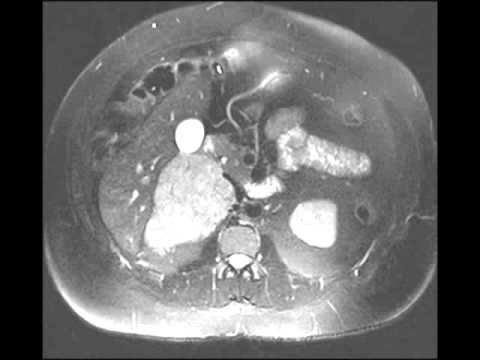

CT Evaluation of Primary Adrenocortical Carcinoma Part 2